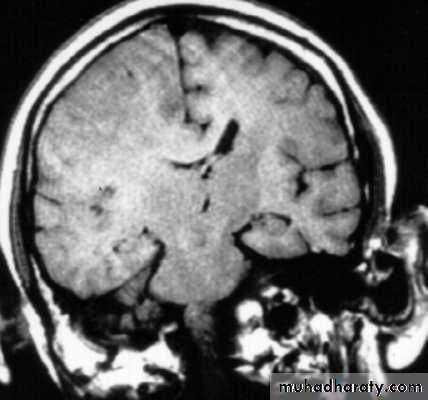

7. Cerebral Herniation

a. Subfalcine Herniation

b. Uncal Herniation

c. Tentorial Herniation

d. Tonsillar Herniation

c. Subfalcine Herniation